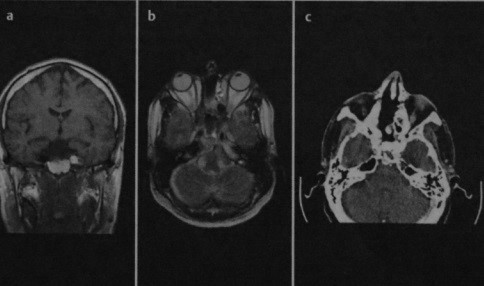

Двусторонняя пневматизация верхушки пирамиды височной кости. Изображение при КТ напоминает аэрированные трабекулярные структуры сосцевидного отростка.

Асимметричная жировая инфильтрация верхушки пирамиды височной кости. Обнаружена случайно при МРТ на основании высокой интенсивности сигнала на Т1- (а) и Т2-взвешенном изображении (b). На КТ (с) определяется нормальная структура кости со значениями поглощения, соответствующими жировой ткани, и отсутствием признаков объемного образования.